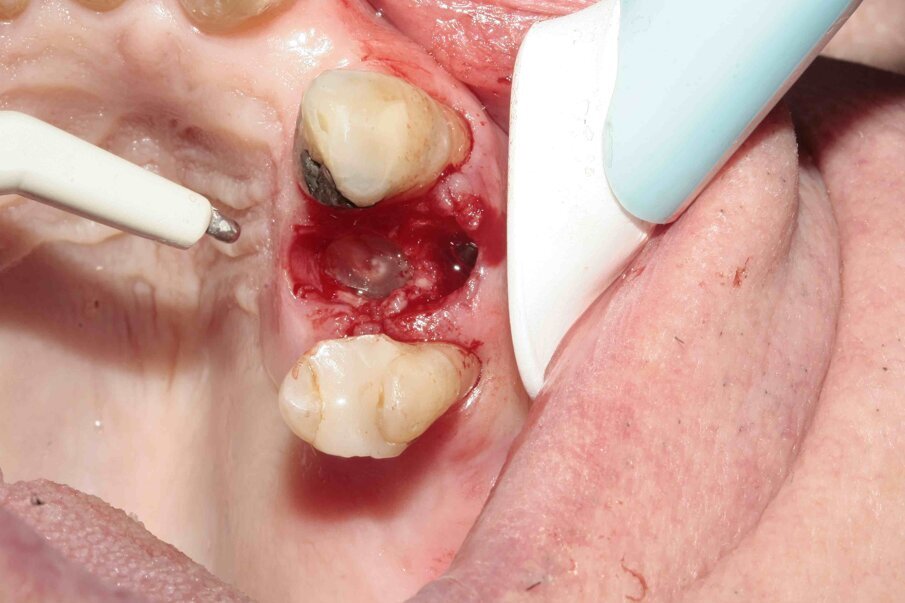

Fig. 8: The tooth was removed with the help of diamond tweezers.

Fig. 9: During luxation, the palatal root was partially fractured while in the alveolus.

Figs. 10–12: The fractured root was carefully luxated with Luxator P1 and Luxator L3S.